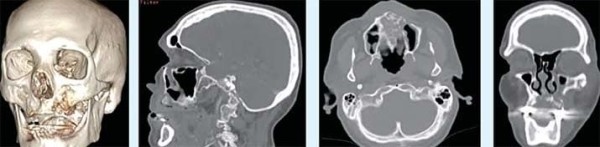

В лучевой диагностике мы увидим на фоне заболевания остеонекроз в бассейне верхнечелюстной артерии (см. фото 2–3). Это ранние признаки проявления некроза, которые четко указывают на то, что ждать больше нельзя — требуется хирургическое устранение очага. В ином случае омертвление тканей будет распространяться дальше.

Фото 2. МСКТ костей лицевого отдела черепа и сагиттальная проекция. Остеонекроз в бассейне левой верхнечелюстной артерии.

Фото 3. КЛКТ в просмотровом режиме MPR. Остеонекроз альвеолярного отростка справа, стенок правой верхнечелюстной пазухи, решетчатой кости справа, нижней и медиальной стенок правой орбиты.